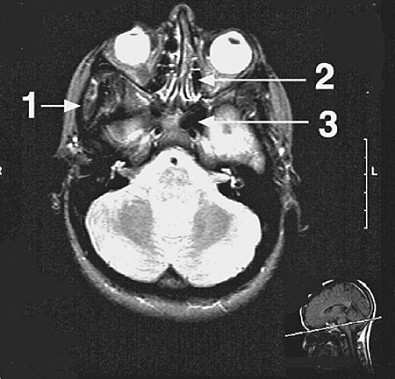

The structure indicated by arrow 2 in following figure, is which of the following?

Answer(s): A

Explanation:

This axial scan is at the level of the orbits as indicated by the insert at the bottom right and the eyeballs in the orbits. Arrow 2 points to the ethmoidal sinus located medial to the orbits. The sinus is divided into compartments by the air cells. The maxillary sinus (choice D) and the inferior nasal meatus (choice B) are located inferior to the level of this scan and are not seen. The sphenoidal sinus (choice E) is indicated by arrow 3 and the infratemporal fossa (choice C) by arrow 1.

A stroke resulting from obstruction of the structure indicated by arrow 1 in following figure, may result in ischemia in which of the following brain regions?

Answer(s): C

Arrow 1 points to the right internal carotid artery which supplies the anterior and middle cerebral arteries in the brain. The territory of the right anterior cerebral artery includes the rightmedial aspect of the frontal lobe, which will be affected by obstruction of the internal carotid artery. Broca's (choice A) and Wernicke's (choice E) areas are located in the majority of the population in the left cerebral hemisphere and are supplied by the left middle cerebral artery from the left internal carotid artery. They will not be affected in this case. The cerebellum (choice B) and pons (choice D) receive their blood supply from the basilar artery (arrow 2) which is formed from the vertebral arteries.